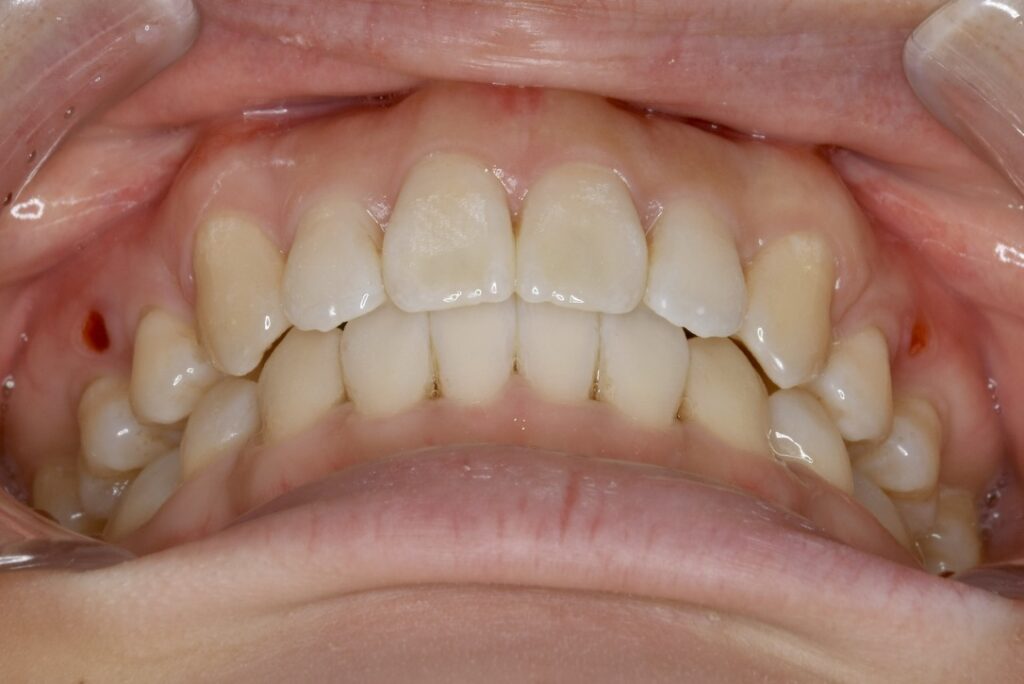

| 主訴 | 前歯の隙間が気になる。 |

|---|---|

| 診断名・主な症状 | 左側犬歯のクロスバイトを伴う空隙歯列 |

| 年齢 | 22歳 |

| 治療内容 | 上の歯のスペースを閉じつつ、下の歯を後ろに下げました。 |

| 使用装置 | マウスピース矯正装置(インビザライン) |

| 抜歯部位 | 抜歯なし |

| 治療期間 | 1年10ヶ月 |

| 通院回数 | 14回 |

| 費用 | 86万円程度(税別) |

| リスク・副作用 | 痛み、歯肉退縮、歯根吸収、抜歯に伴う出血や腫れが生じることがあります。 |